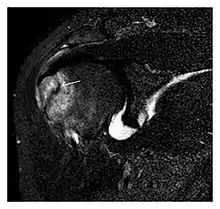

The greater tuberosity of the humerus is also an illustrative location of occult fractures. The osseous injury may follow seizures, glenohumeral dislocation, forced abduction, or direct impaction. They are commonly discovered on MRI in symptomatic patients with suspicion of rotator cuff tear. Coronal images are best suited for detection. They appear as crescentic oblique lines surrounded by a bone marrow edema pattern (Figure 5). The rotator cuff must be inspected since associated ligamentous lesions are common. In the ankle, malleoli and tarsal bones should be checked carefully for any cortical disruptions and radiolucent lines that may reveal a fracture. Awareness of the exact location of the pain will help direct the attention of the interpreter when searching for very subtle signs of fracture (Figure 6).[1]

- a

- b

Figure 13: Partial osseous avulsion of the gluteal muscles at the greater trochanter in a 59-year-old man who presented with the right hip pain without a history of trauma. Lauenstein view and anteroposterior and radiographs (not shown) did not show an obvious fracture line or disruption of bony contours in the acetabulum or the right femoral neck. (a) Coronal T1-weighted MRI displays an incomplete fracture line extending partially from the greater trochanter (arrow). (b) Coronal short tau inversion recovery MRI shows heterogeneous hyperintensity in the same region (arrow) as well as hyperintensity within the gluteus medius and minimus muscles (arrowheads) consistent with tissue edema and hematoma.[1]